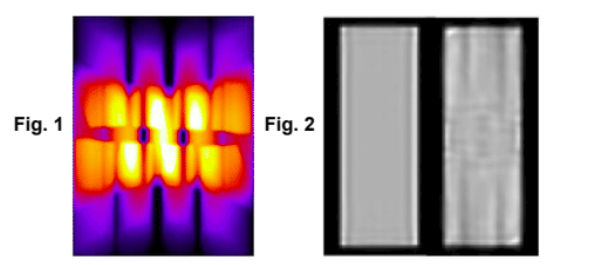

| ABSTRACT | Introduction: Simultaneous in-vivo imaging of several biological processes may improve oncological, neurological and cardiovascular studies by providing complementary information obtained under the same exact conditions and coregistered in space and time. Standard PET imaging does not allow multiplexed acquisitions, as all annihilation photons have the same energy. We developed a technique called multiplexed PET (mPET), which uses a tracer labelled with a pure positron emitter (such as 18 F, 13 N, 11 C), and a tracer labeled with a positrongamma emitter (such as 124 I, 76 Br, 82 Rb, 86 Y). Positrongamma emitters generate a significant number of triplecoincidences , which allows them to be differentiated from the standard PET radionuclides . In this work, we evaluated the performance of mPET using phantom and animal experiments. |

| ABSTRACT | When multiple pinholes are used to acquire SPECT projection data, there may be regions on the detectors where data from two or more pinholes overlap. Such “multiplexing” of projection data can cause artifacts and/or increased noise in reconstructed SPECT images, depending on the exact acquisition geometry. We previously described a modified MLEM algorithm that alternates between (i) estimating the separated projection data that would be obtained through each individual pinhole (i.e., demultiplexed data), based on the current MLEM iteration’s image, and (ii) reconstructing the SPECT image by MLEM, but assuming that the demultiplexed data estimates are the actual measured data. The modified MLEM algorithm was first tested with data simulated for a stationary 39pinhole collimator tube, and more recently with Tc99m phantom data acquired from three vials of different sizes on a 6pinhole, tripledetector SPECT camera. |

| JOURNAL | IEEE Nuclear Science Symposium & Medical Imaging Conference, 2014 |